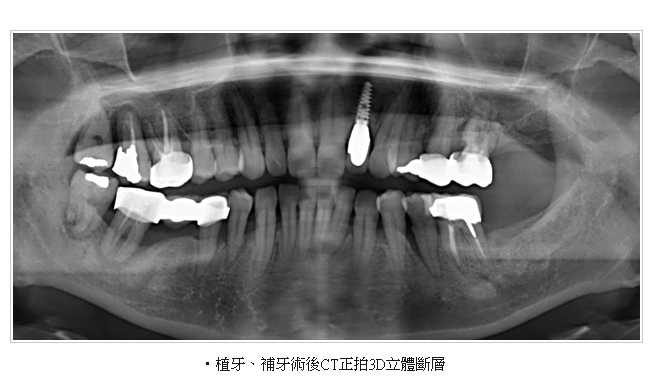

電腦斷層掃描合成3D影像,術前準確模擬植牙角度及位置。

美國口腔顎面放射學會-AAOMR (The American Academy of Oral and Maxillofacial Radiology)2001 年研究文獻指出,從事植牙手術前醫師除了透過全口X光影像、根尖片影像觀察近遠心距離外,應再拍攝電腦斷層(CT)影像,藉由切面影像(Cross-sectional view)以事先評估出齒槽骨寬度、舌頰側的距離、骨質及組織的密度,才能提昇植牙手術的安全性。